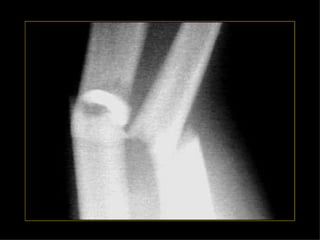

HOMBRO BRAZO CODOANTEBRAZO MUÑECA MANO Monteggia Colles Fx escafoides

HOMBRO BRAZO CODO ANTEBRAZO MUÑECA MANO Monteggia Colles Fx escafoides